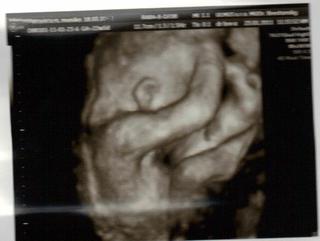

dnes sme boli na tom 4D... no naša malá potvora sa nám ukázala iba na malinkú chvíľočku a potom ani za nič 😀

tak o 2 týždne ideme zasa ale už ju nebude merať už iba kvôli videu aby sme mali peknučké lebo teraz nie je skoro nič v 4 D , lebo to nebolo riadne vidieť.. Keď to mmm donahráva na youtube hodím vám sem link.. malo by to ešte takých 20 minút trvať.

Malinká je krásna a váži cca 572 g 😀 Zodpovedáme 23 tt a 2 d.. sme 22 tt a 5 d... takže je to ok 🙂

STále mala ručičku pred tváričkou 😀

alena24 to mi je luto, že malinky takto "štrajkoval" a neukázal sa v plnej kráse....a tak si sa tešila. Chystáš sa tam este raz?

@alena24 - vidím, že váš je ako naša .-D tiež tie ruky pred tvárou. ale aspoň zo začiatku na chvíľu ukázala.. 😀

o 2 týždne si to zopakujeme. som zvedavá či to aj ona zopakuje 😀